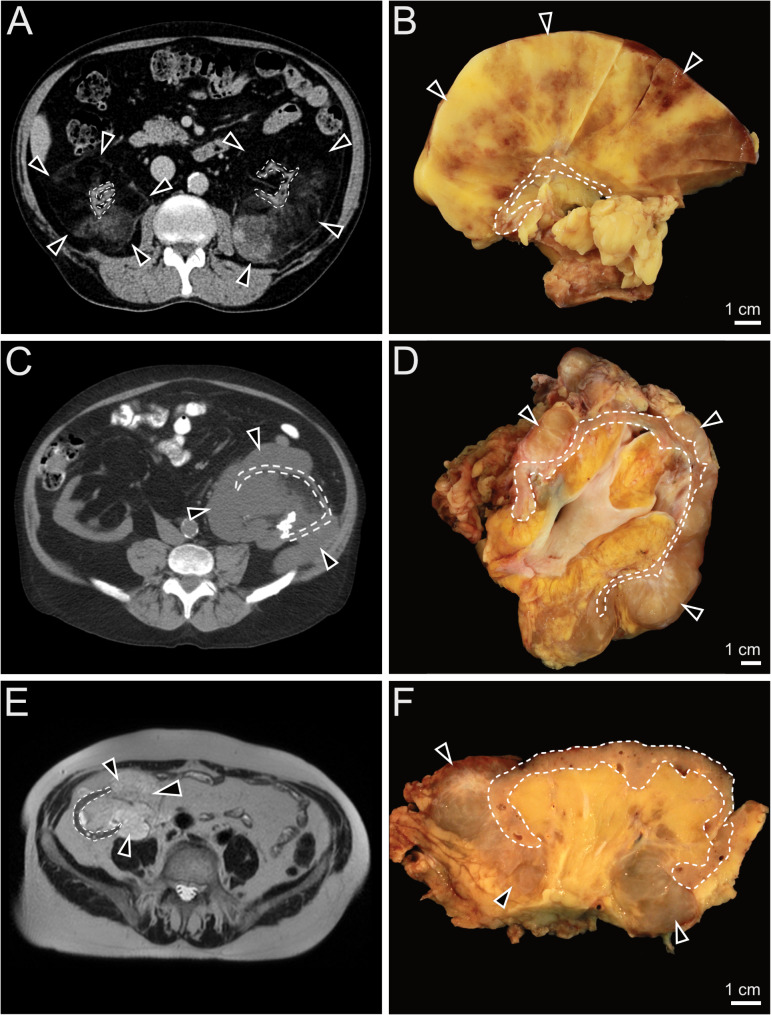

Case presentation: This report describes three cases of PMPF in patients following renal transplantation, involving both native and grafted kidneys. Macroscopically, all cases consisted of shrunken kidneys with thinned and atrophic renal parenchyma surrounded by massively hypertrophic perirenal fat with mass-forming nodules, which was in concordance with cross sectional imaging findings acquired before surgery. Histology of the remaining renal parenchyma showed end stage renal disease in all four surgically removed kidneys, with diffuse interstitial fibrosis, tubular atrophy and sclerosed glomeruli. Perirenal adipose tissue consisted of mature fat with areas of significant myxoid and collagenous stromal component, interspersed with bland spindle and stellate-shaped cells. Immunohistochemistry for S100, smooth muscle actin, desmin and IgG4 were negative. No MDM2 gene amplification was identified by fluorescence in situ hybridization. Broad molecular profiling using the FoundationOne®Heme assay revealed no evidence of pathogenic alterations on DNA and RNA levels.

Conclusion: PMPF is a rare benign condition typically associated with chronic kidney disease, occurring late in the course. The radiological findings may be mistaken for those of a malignant tumor, and histopathological examination is required to exclude a malignant neoplasm, in particular a well-differentiated or dedifferentiated liposarcoma of the retroperitoneum. Renal transplant recipients can be affected by PMPF, which can occur in both native and transplanted kidneys several years following renal transplantation.